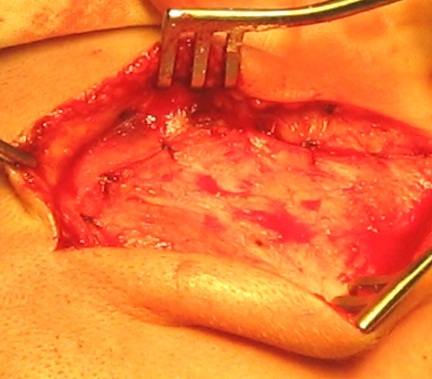

A hígítás után a bőr metszés és az expozíció a csonthártya és fascia halántéki izomzatot csonthártya lebeny otseparovyvayut és előrelépni, tedd visszahúzó (3. ábra).

3. ábra - a kialakulását a bőr és a periostealis szárnyak